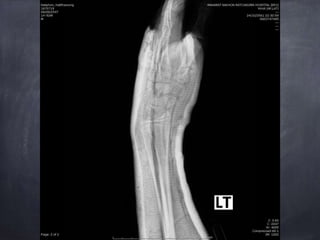

Epiphyseal plate injury Salter harris type 2 Lt.

distal end redius

usually fall on an outstretched hand, extended at wrist

often during sports or play